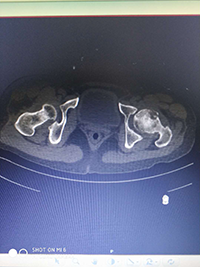

术前影像资料: